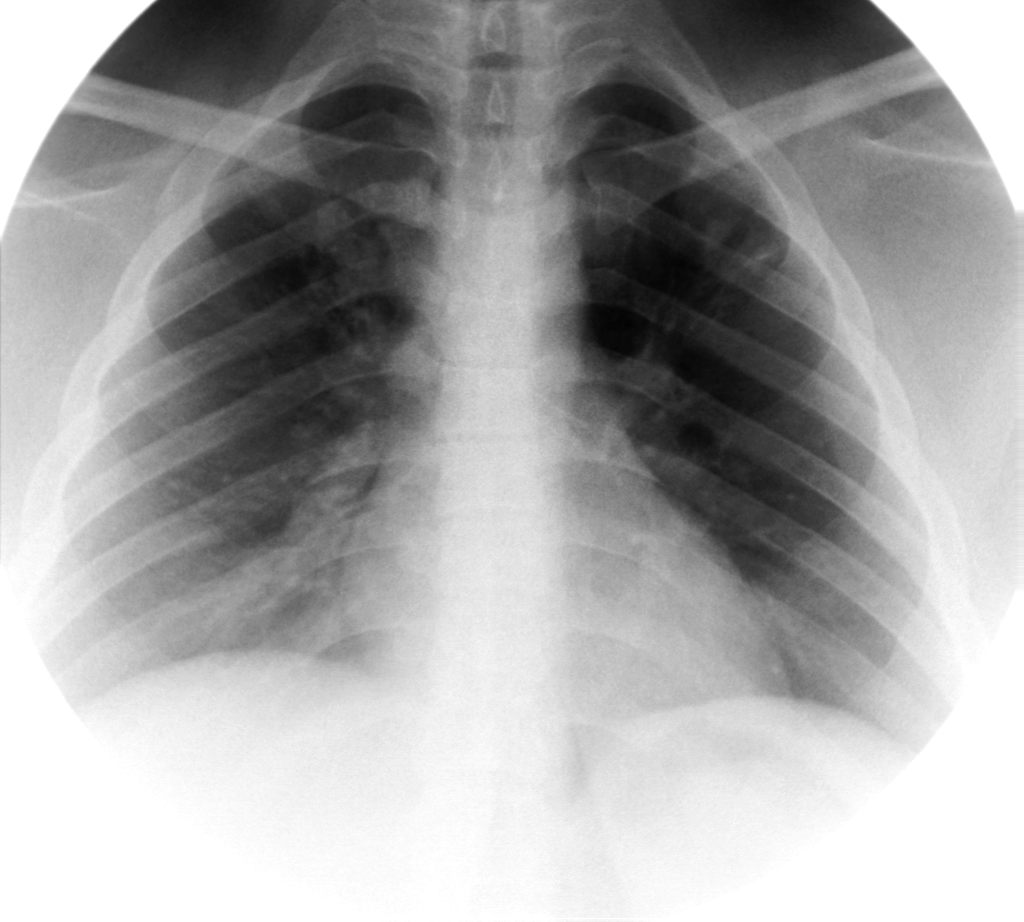

- გულმკერდის რენტგენოგრაფია სტენტირებამდე 10 დღით ადრე

აღინიშნება მარცხენა ფილტვის ჰიპოვენტილაცია და შუასაყარი საგრძნობლად ცდომილია მარცხენა მხარეს.